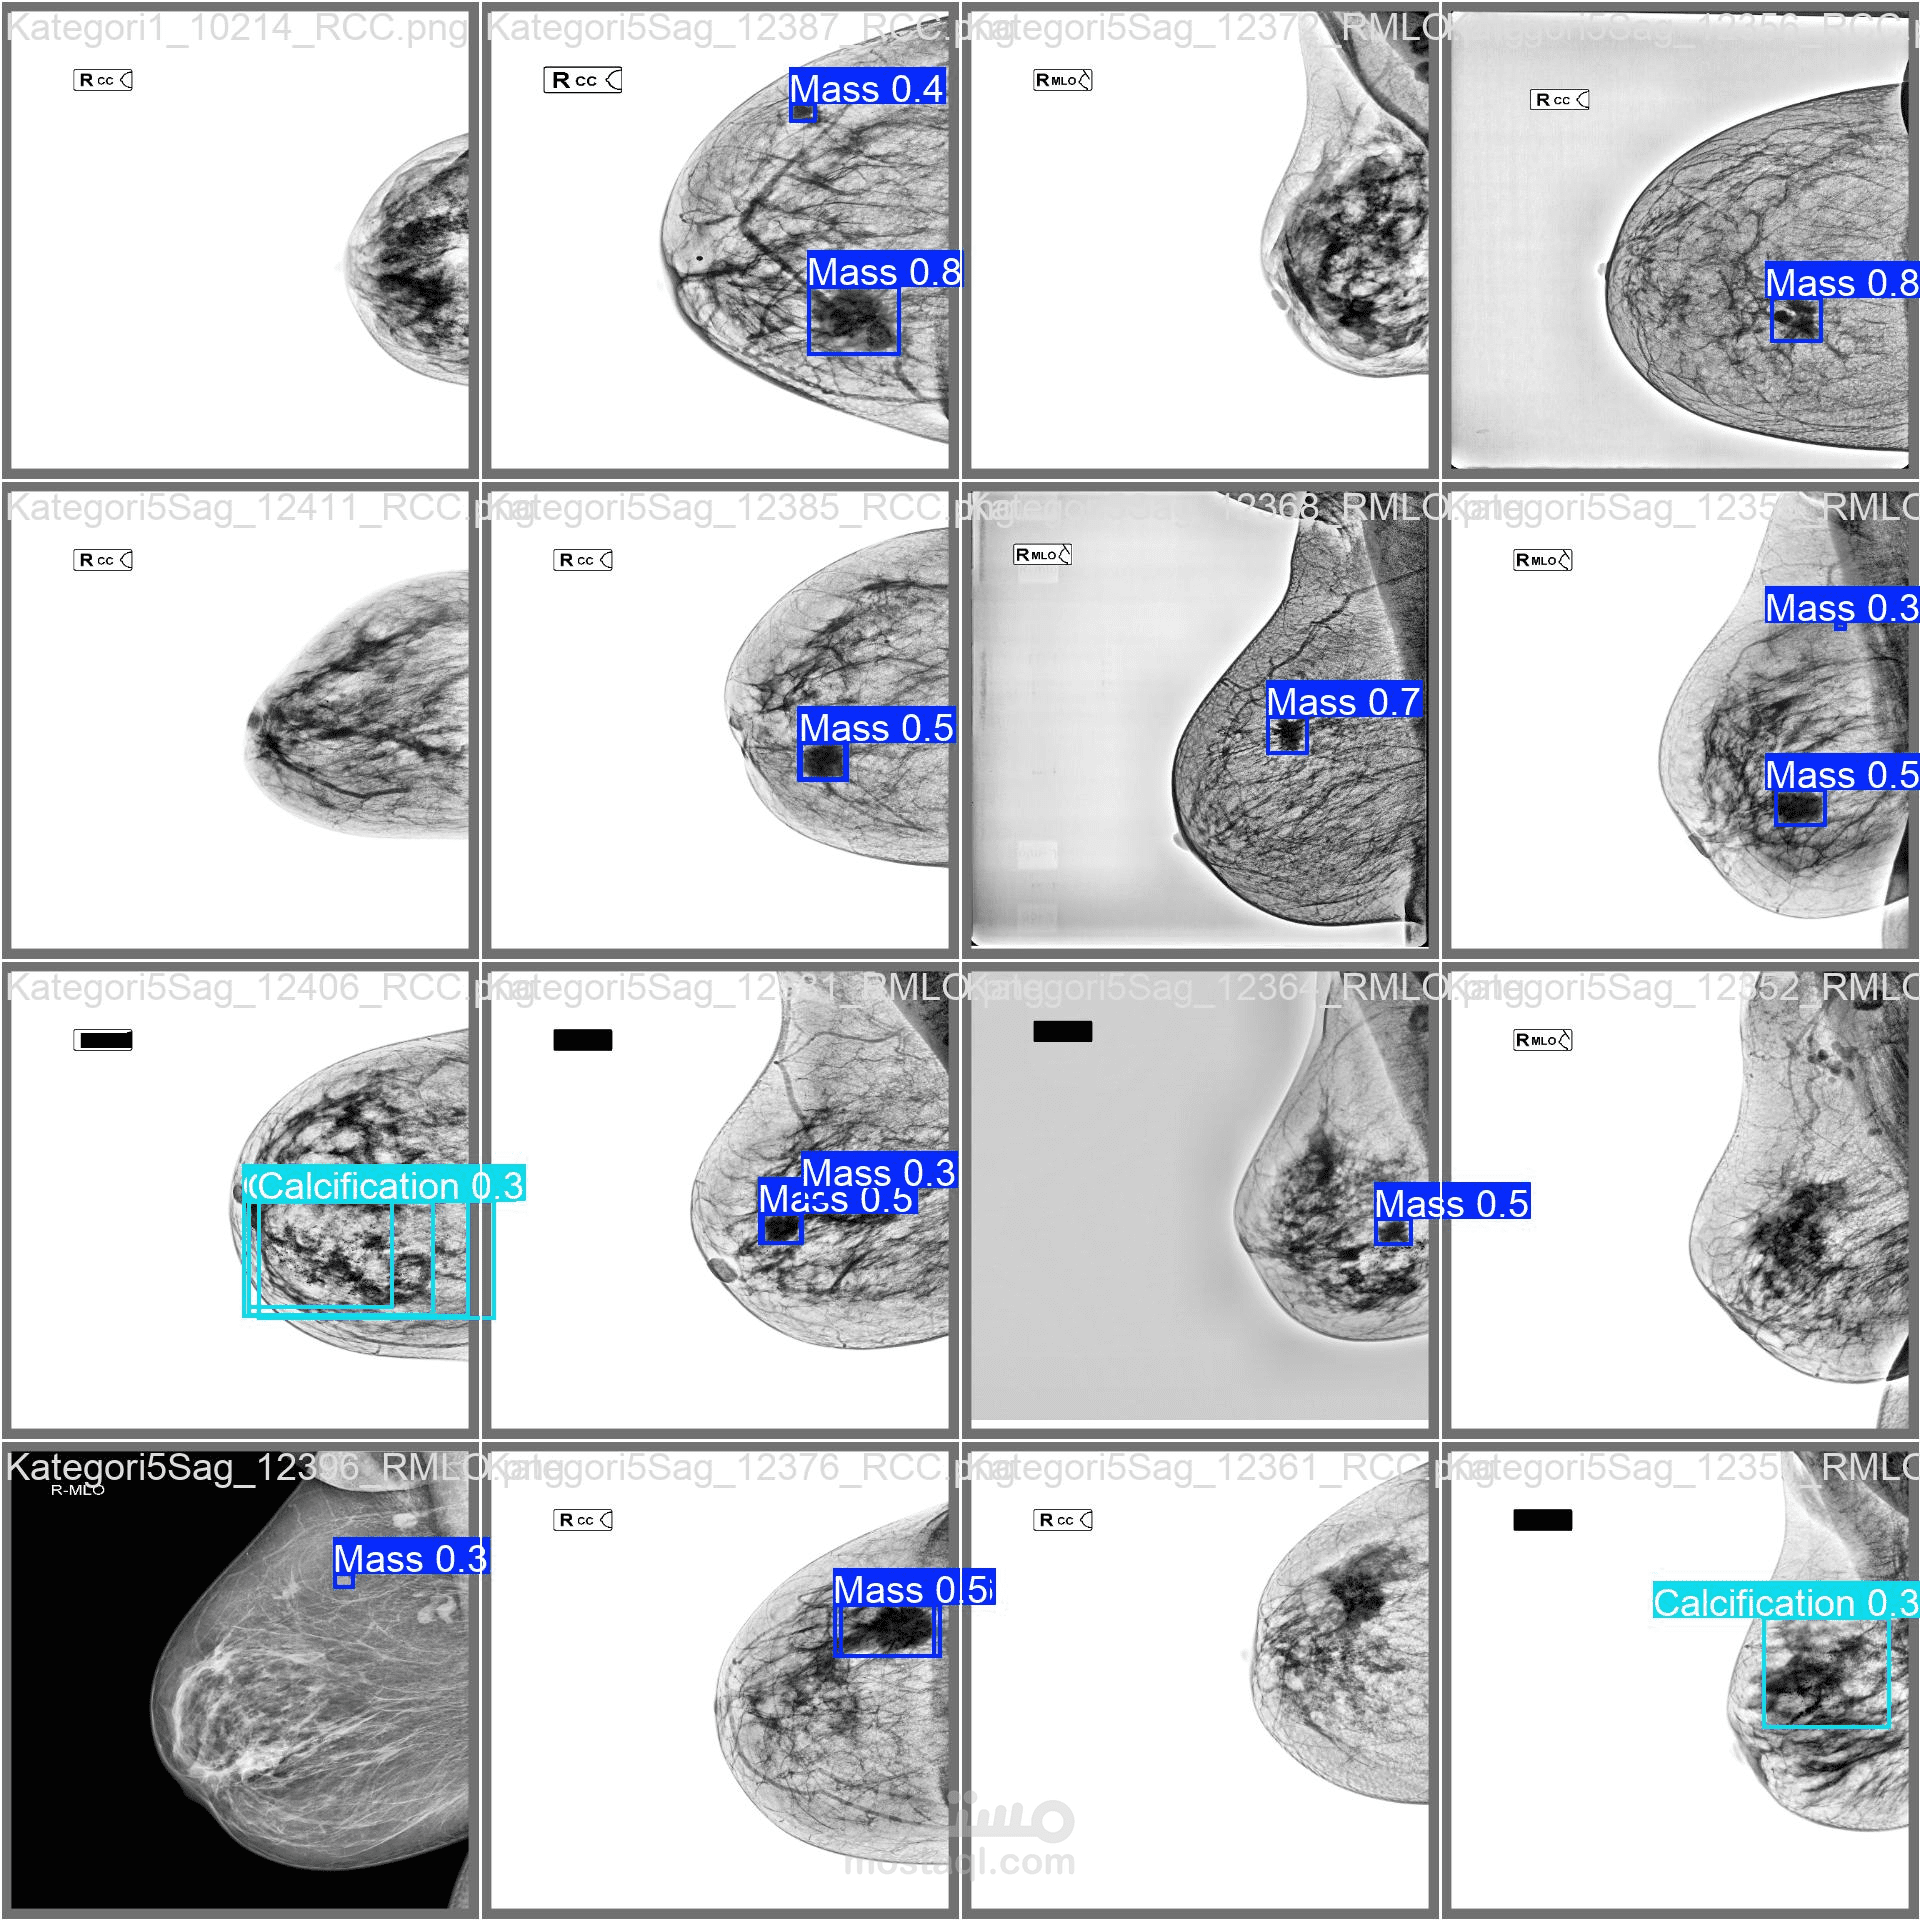

قمت بقيادة فريق "Pixelers" في مسابقة الذكاء الاصطناعي في الصحة ، وحققنا المركز الثالث عشر من بين 5,393 فريقًا مشاركاً. ركز مشروعنا على تطوير نماذج الذكاء الاصطناعي لاكتشاف الآفات في صور الماموغرام، وتصنيف أنواع BIRADS، واستخدام معالجة اللغة الطبيعية (NLP) لتحليل التقارير الطبية. كنت مسؤولاً عن قيادة الفريق، ومعالجة البيانات، وتطوير النماذج باستخدام YOLOv10 لاكتشاف الكتلة والكلس الموجودين في صور الأشعة السينية للثدي و استخدمت نموذج ال U-Net للتقسيم. نجحت في إدارة دمج نماذج التعلم الآلي من مرحلة إعداد البيانات حتى النتائج النهائية، مما ضمن دقة عالية في اكتشاف الكتلة والكلس, وكفاءة في تنفيذ المشروع.